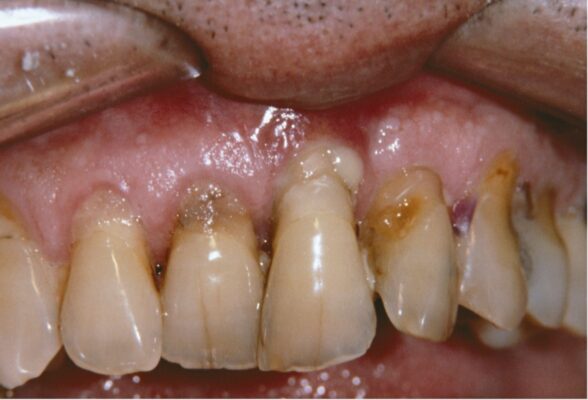

Hình ảnh bệnh nhân bị cao răng, tụt lợi do viêm quanh răng gây nên